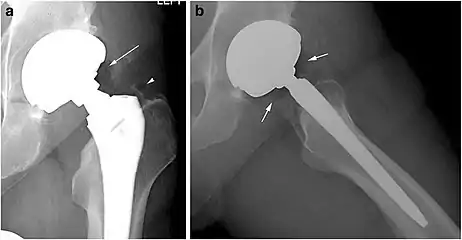

Pneumarthrosis is the presence of air in a joint. Its presentation on radiography is a radiolucent cleft often called a vacuum phenomenon, or vacuum sign.[30] Pneumarthrosis is associated with osteoarthritis and spondylosis.[31]

Pneumarthrosis is a common normal finding in shoulders[30] as well as in sternoclavicular joints.[32] It is believed to be a cause of the sounds of joint cracking.[31] It is also a common normal post-operative finding at least after spinal surgery.[33] Pneumarthrosis is extremely rare in conjunction with fluid or pus in a joint, and its presence can therefore practically exclude infection.[31]